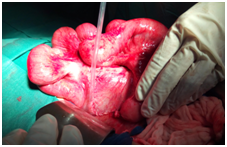

All the patients were explored urgently by midline incisions. The different types of hernia found were through: Paranormal orifice: 3 left paraduodenal (Figures 2) (Figure 3A) (Figure 3B), 2 right paraduodenal, 1 intra-mesosigmoidal and 1 retrocecal. Abnormal pathologic orifice: 2 trans-mesenteric (Figures 4A-4C), 1 in the posterior cavity through a colo-omental dissinsertion hole Figure 5 and 1 trans-omental. The Reduction of the herniated viscera was never a problem but a bowel necrosis was found in two cases, which required dilatation of the hernial orifice and resection of 1, 25m and 60cm of small bowel with immediate restoration of continuity. The closure of peritoneal fossae or an abnormal orifice was done easily with a resorbable suture (Table 2). We had no death in our patients. Two cases of wound infection were reported classified Grade I in the Clavien-Dindo classification of surgical complications. These patients were treated by antibiotics and had local treatment. The length of hospital stay was 8 days (3-11days). In the follow-up, there was no recurrence.

Figure 2 Left paraduodenal hernia, sac opened and the bowel reduced from it.

Figure 3A: Left paraduodenal hernia, sac opened and the bowel reduced from it.